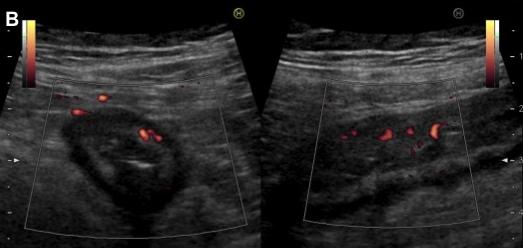

Image radiologique ASP du colite ischemique

est image de : Dilatation ileus du colon , Signe de

empreinte de pouce , intramural aerique dans cas necrose de

la paroi , image de croissante gaszeuse sous diapragmatique

dans cas perfore .

Image radiologique ASP

d'une colite ischemique : Image empreinte en

doigtier sur le colon trans verse et colon

descendant |

Image de aerique du colon et

image en empreinte de pouce ( fleche noire ) . du

colon transverse et colon descendant |